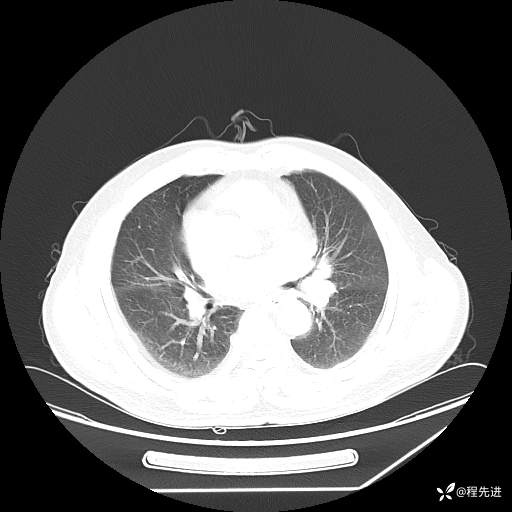

患者性别:男

患者年龄:57岁

简要病史:声嘶2月余

CT平扫+增强: